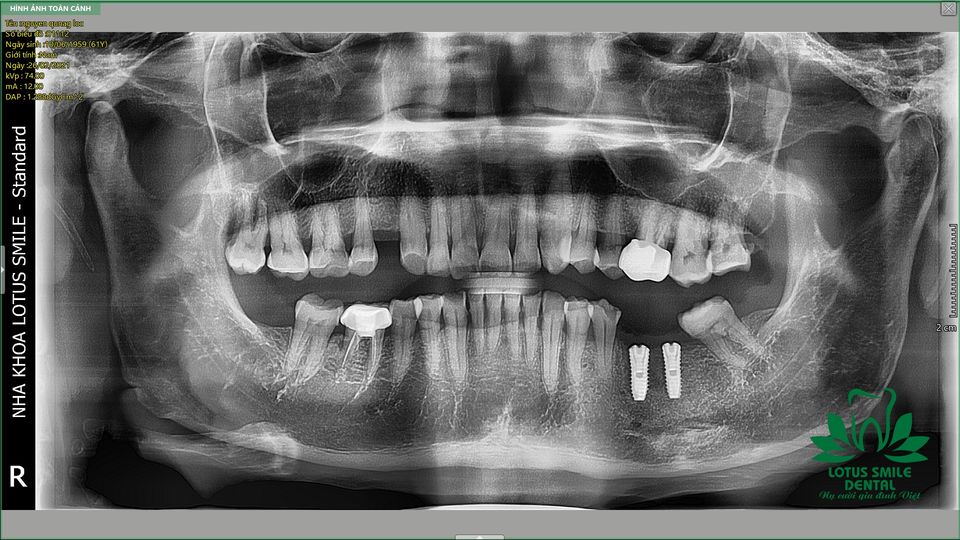

Ca cấy ghép 2 trụ imjplant của bệnh nhân 62 tuổi đến từ Quảng Nam tại Nha khoa Lotus Smile Đà Nẵng 💚

CHỤP PHIM CT CONE BEAM CÔNG NGHỆ CAO